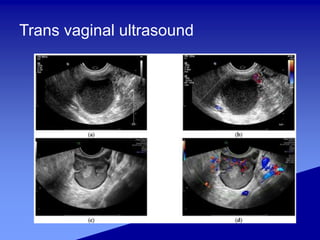

Trans vaginal ultrasound